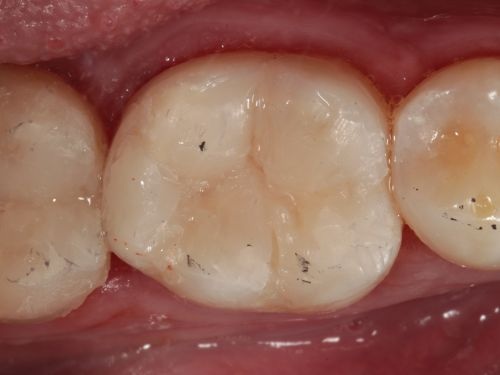

A 35-year-old male presented to the clinic to replace some inadequate restorations, one of which was for the lower right first molar (Fig. 1). For this tooth, the molar was restored with composite resin using the direct technique. The operative field was isolated, the old restoration was removed, and surface hybridization was completed using Futurabond U universal adhesive from Voco (Fig. 2). After placing a sectional matrix and a spacer ring, the composite resin (Voco’s GrandioSO 4U, shade A2) was placed in the proximal box with a thickness less than 4 mm, which is the maximum recommended thickness for the chosen material (Fig. 3). Additional increments of composite resin were applied to complete the anatomical stratification. The final morphology was sculpted, followed by light-curing to ensure complete polymerization (Fig. 4). The rubber dam was removed (Fig. 5), and the occlusion was adjusted using a finishing carbide bur with 12 blades (Fig. 6). Finishing and polishing was completed, with the final result shown in the Figures 7 and 8.